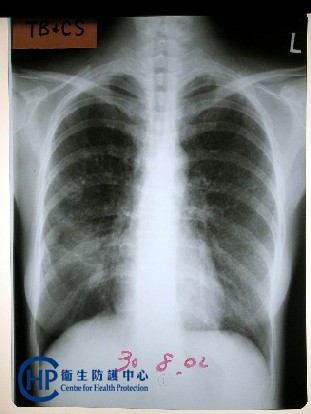

肺結核(pulmonary tuberculosis)俗稱的肺癆,是由結核分枝桿菌 感染人體肺部引起的一種慢性傳染病, 是結核病中最常見的一種。 典型肺結核起病緩漸,病程經過較長,常見症状有低熱、乏力、食欲不振、咳嗽和咯血等。 但多數患者常無明顯症状,經x線檢查時才被發現;有些患者則因咯血才去檢查就診。